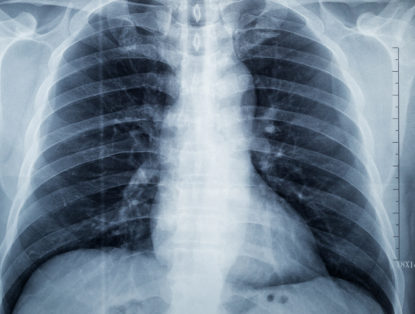

Posted on March 14, 2022

ImageCare Radiology provides a wide range of services for diagnostic medical imaging in New Jersey, including imaging for diagnosing blood clots. ...

Read More